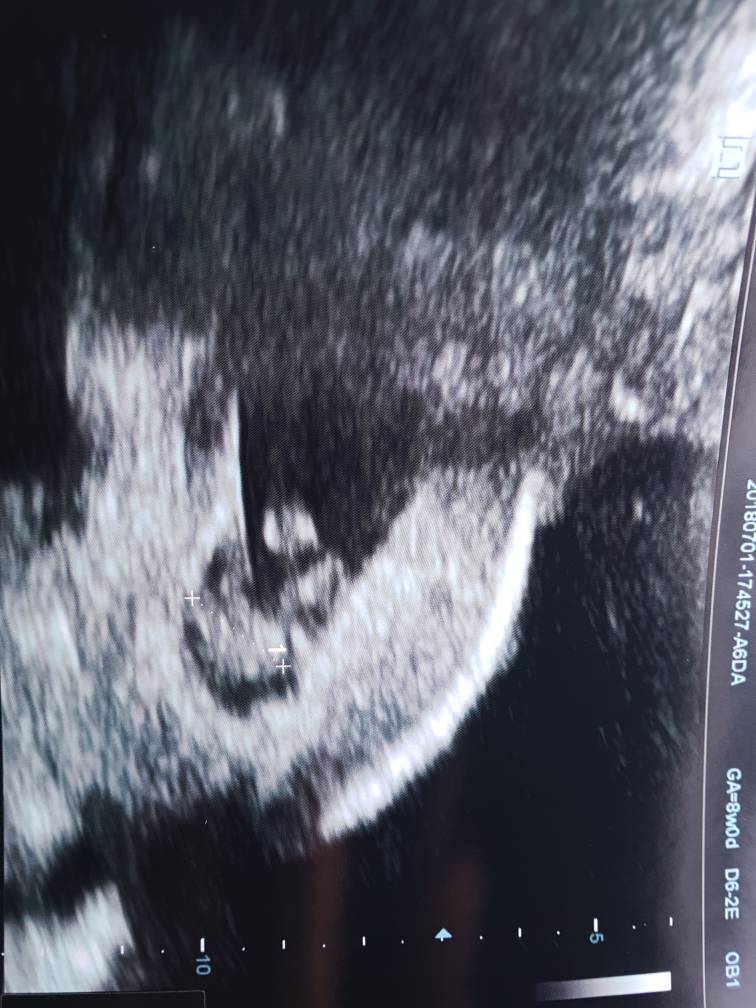

Ale super! Gratulacje! To który dokładnie tydzień pokazuje USG?Hej dziewczyny my juz po wizycieŻabka rośnie, serduszko 173 uderzenia na minute I mierzy juz 1.4cm

BuziakiZobacz załącznik 872765Zobacz załącznik 872766

Dzis jest 8tyg 0d, wg usg 7tyg 6d![]()